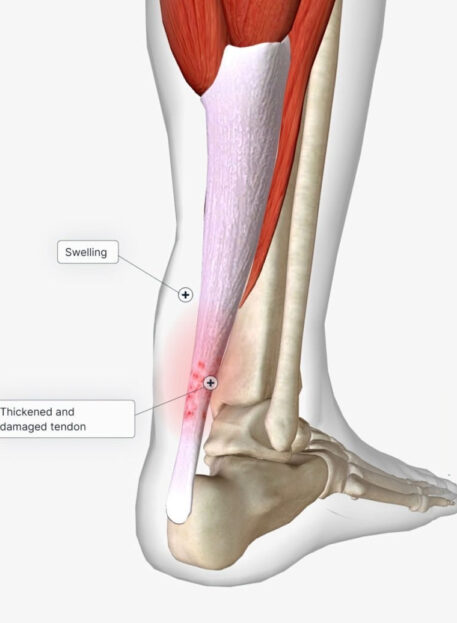

Lezije Ahilove

TETIVE

01. Vrste poškodb Ahilove tetive

- Peritendinitis – vnetje tetivne ovojnice

- Tendinitis / Tendinoza – degenerativne in vnetne spremembe v tetivi

- Ruptura (raztrganina) – delna ali popolna pretrganost tetive

02. Simptomi lezij Ahilove tetive

- Bolečina v zadnjem delu gležnja ali peti

- Oteklina in občutek toplote

- Zategnjenost mečnih mišic

- Težave pri hoji, teku ali stoji na prstih